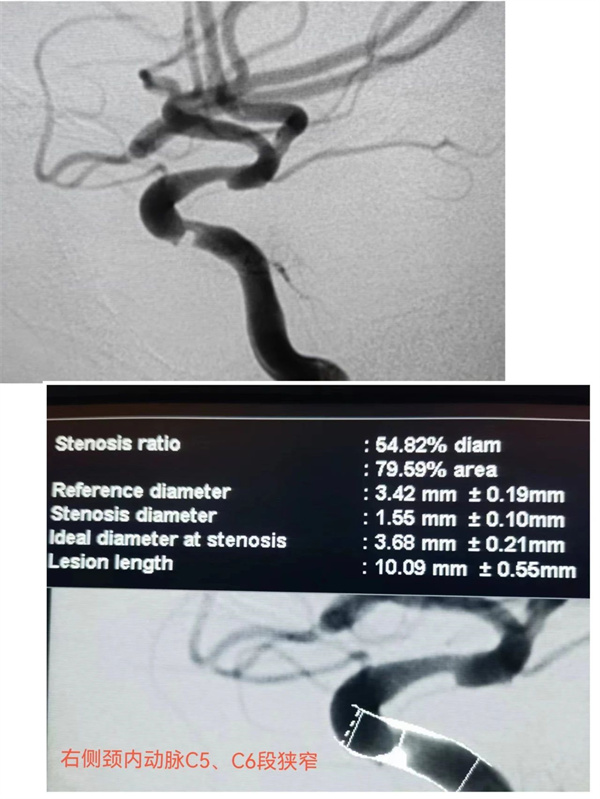

患者贾某,男,48岁,因“反复发作头晕伴肢体乏力一周”来到萍乡市第二人民医院入住神经外科,入院诊断“脑梗死”,经查:1、头颅MRI:右枕顶叶及半卵圆中心多发急性脑梗塞;2、颅脑MRA:右侧颈内动脉C5、6狭窄。

入院后,以李金亮主任为首的神经外科团队组织科内会诊,讨论后在局麻下行经股动脉全脑血管造影术。脑血管DSA造影提示:右侧颈内动脉C5段重度狭窄,狭窄率约80%,C6段轻度狭窄,狭窄率约40%。